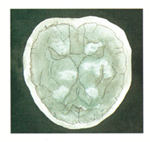

¡á ³ú : ³úÁ¹Áß(Áßdz)

- Çѱ¹Àο¡°Ô °¡Àå ¸¹Àº ÇÕº´Áõ